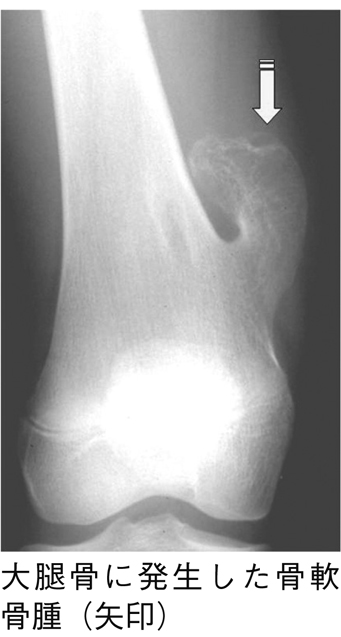

良性骨腫瘍 日本整形外科学会 症状 病気をしらべる